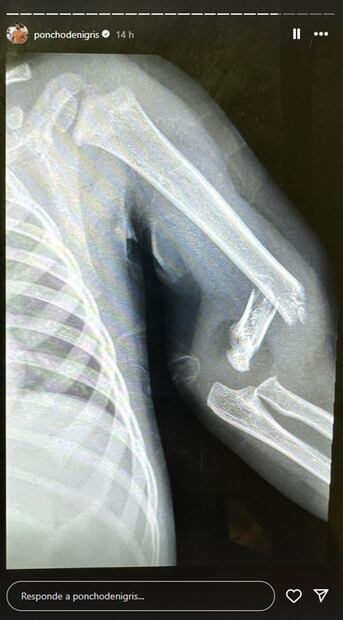

Poncho de Nigris dio a conocer que la operación de Toñito, su hijo más pequeño, fue todo un éxito y ya encuentra recuperándose, luego de que se rompiera un brazo, mientras jugaba con sus hermanos y su papá el día de ayer.

Este miércoles, el hijo de Poncho sufrió una caída que produjo que se rompiera uno de sus brazos, así lo dio a conocer el conductor en su cuenta de Instagram.

"Les quiero contar antes de que se enteren por otra parte, tuvimos un accidente leve, se quebró un bracito Toño, por andar jugando en la calle, yo le sentí el bracito como safado, cayó mal, se le hizo para atrás el brazo".

"Fue error mío, se me hace, no es nada grave pero sí lo van a tener que operar y ponerle clavos, no es nada grave pero se siente feo, se siente horrible que se quiebre un brazo de uno de tus hijos, el hecho de verlo llorar de dolor y, más si es tu culpa, bueno... no es culpa de nadie, tienes que estar al tiro, son accidentes que pasan", compartió.

"Entró a quirófano, que suena a algo muy mayor, con sedación, con anestesia, en dos semanas tiene que tener inmovilidad su bracito, la verdad sí me dio mucho pánico, no me había pasado con un hijo", señaló.